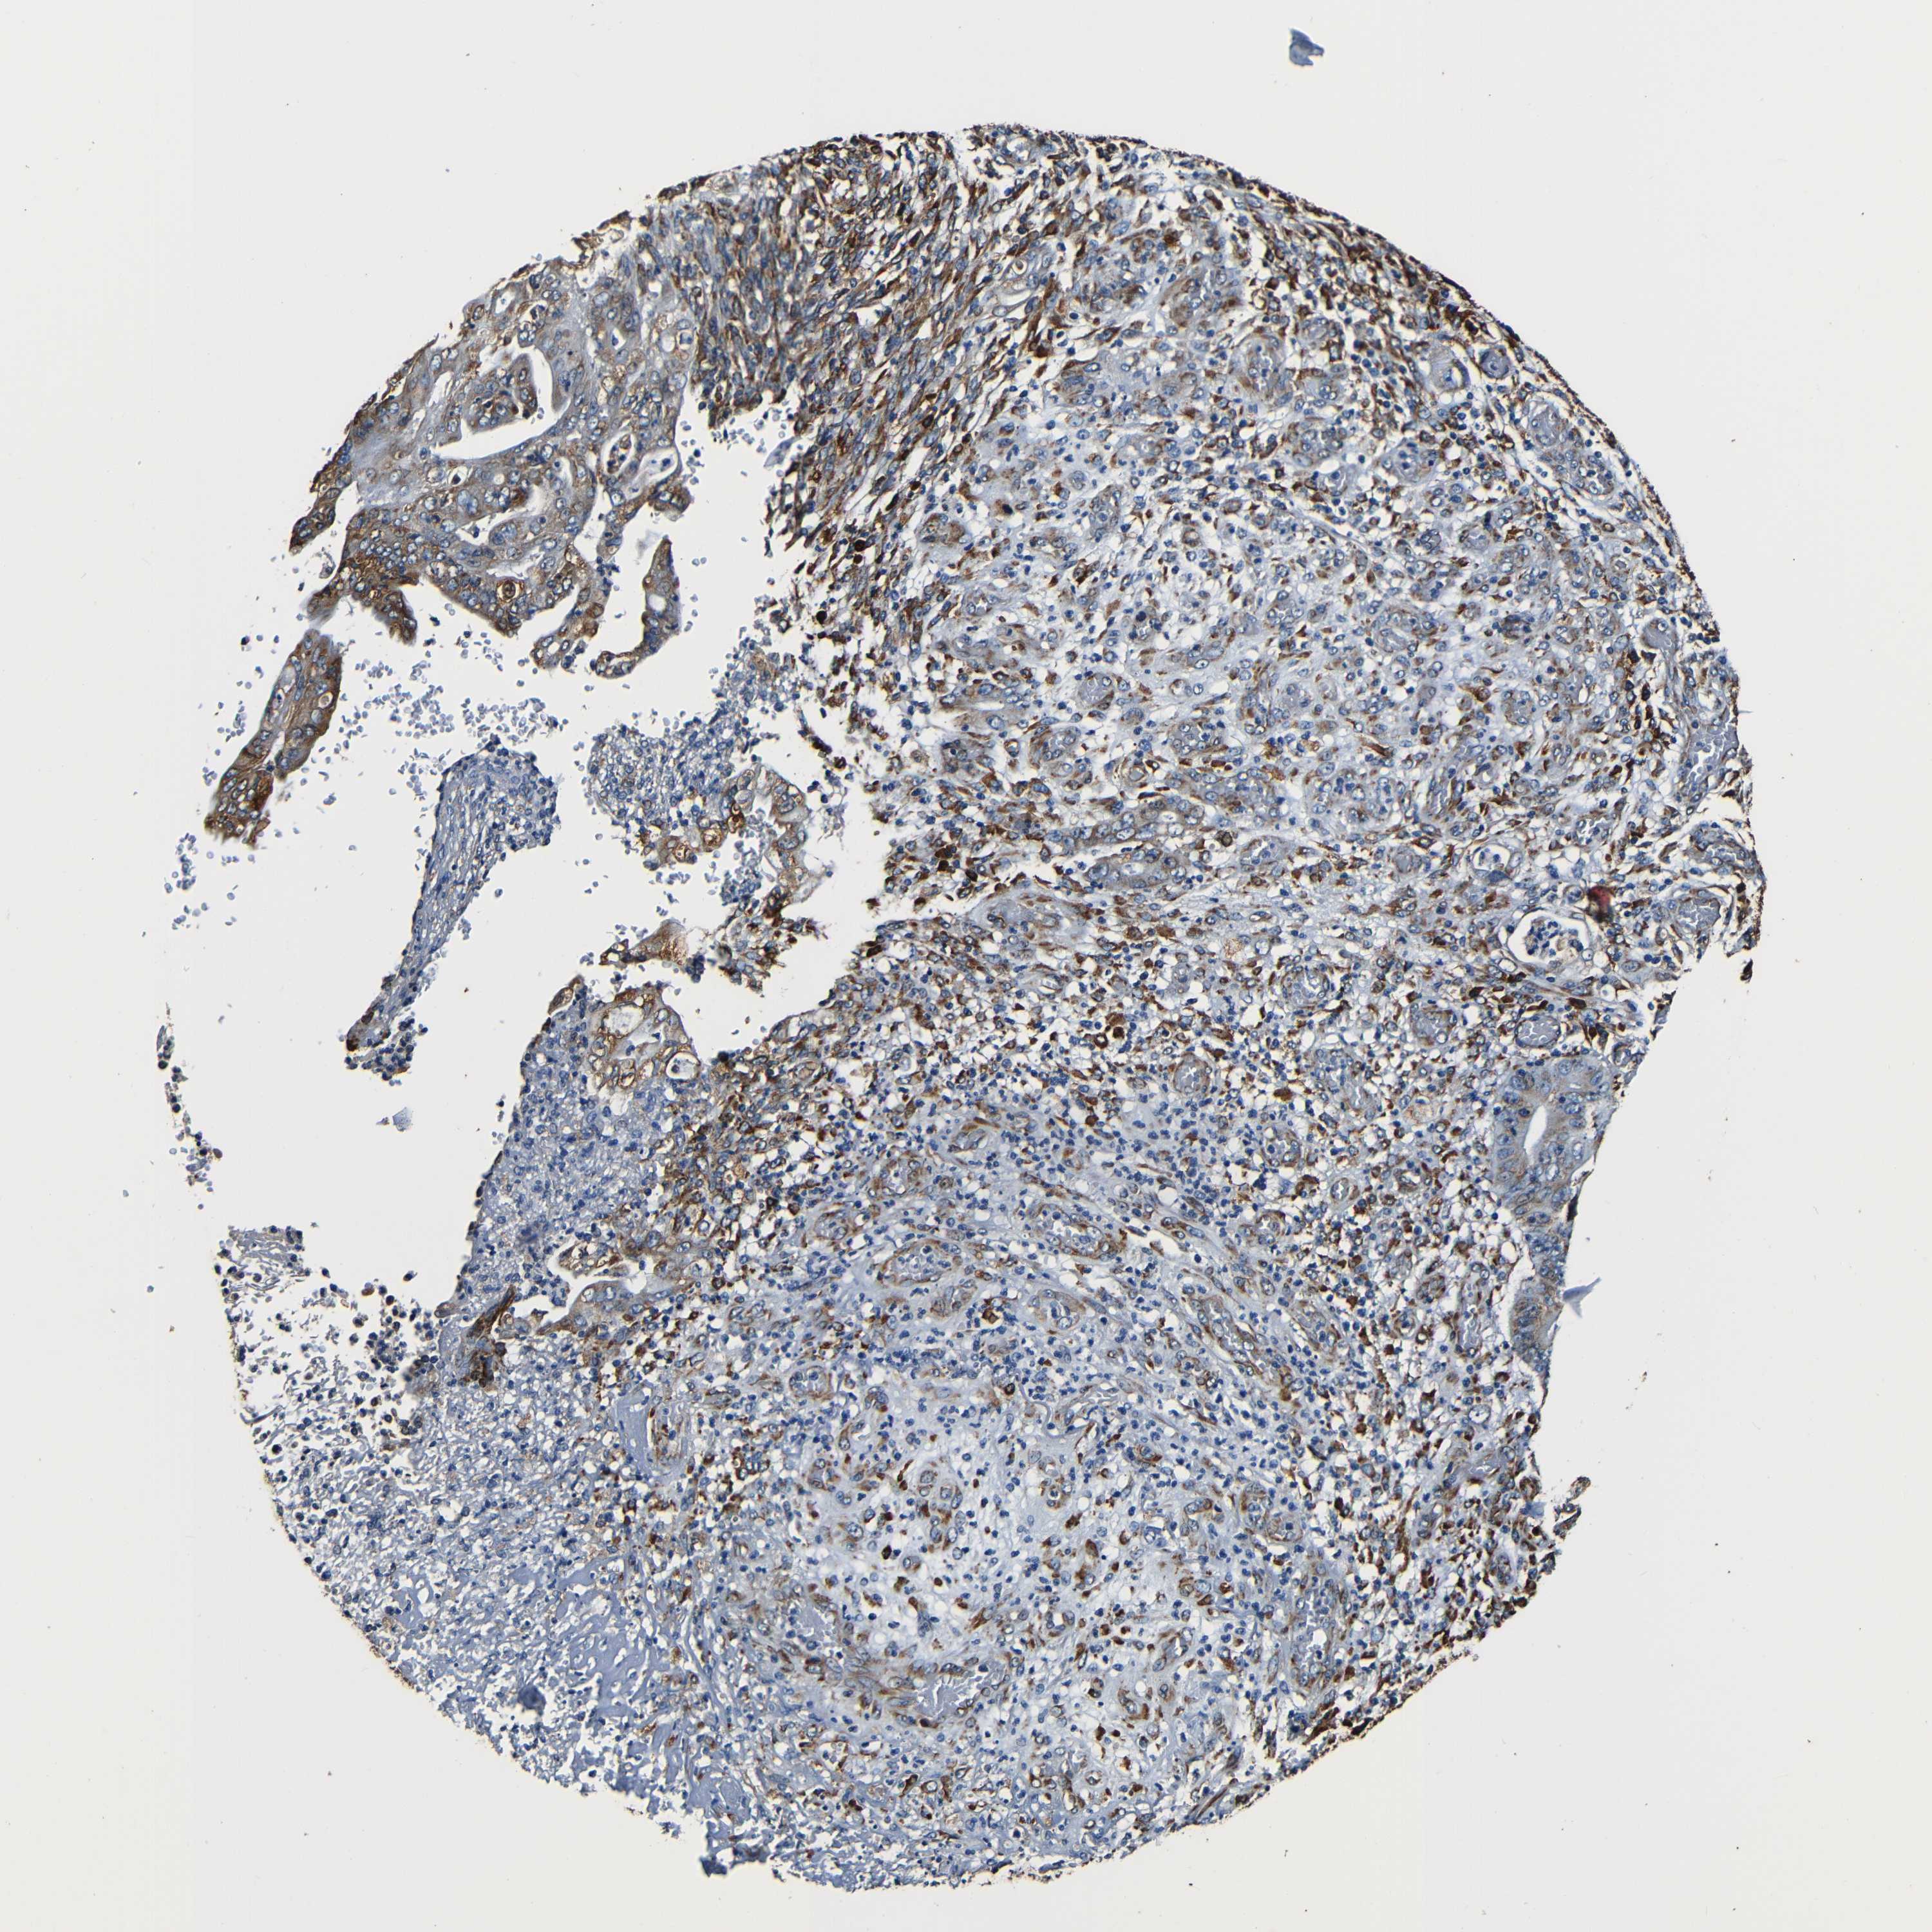

STOMACH CANCER - Protein expressioni

A mouse-over function shows sample information and annotation data. Click on an image to view it in a full screen mode. Samples can be filtered based on level of antibody staining by selecting one or several of the following categories: high, medium, low and not detected. The assay and annotation is described here.

Note that samples used for immunohistochemistry by the Human Protein Atlas do not correspond to samples in the TCGA dataset.

Antibody stainingi

Antibody staining in the annotated cell types in the current human tissue is reported as not detected, low, medium, or high, based on conventional immunohistochemistry profiling in selected tissues. This score is based on the combination of the staining intensity and fraction of stained cells.

Each image is clickable and will lead to virtual microscopy that enables deeper exploration of all samples and also displays staining intensity scores, fraction scores and subcellular localization as well as patient and tissue information for each sample.

Antibody HPA009026

Antibody HPA011924

Staining

High

Medium

Low

Not detected

Intensity

Strong

Moderate

Weak

Negative

Quantity

>75%

75%-25%

<25%

None

Location

Nuclear

Cytoplasmic/membranous

Cytoplasmic/membranous,nuclear

Adenocarcinoma, NOS

Adenocarcinoma, High grade